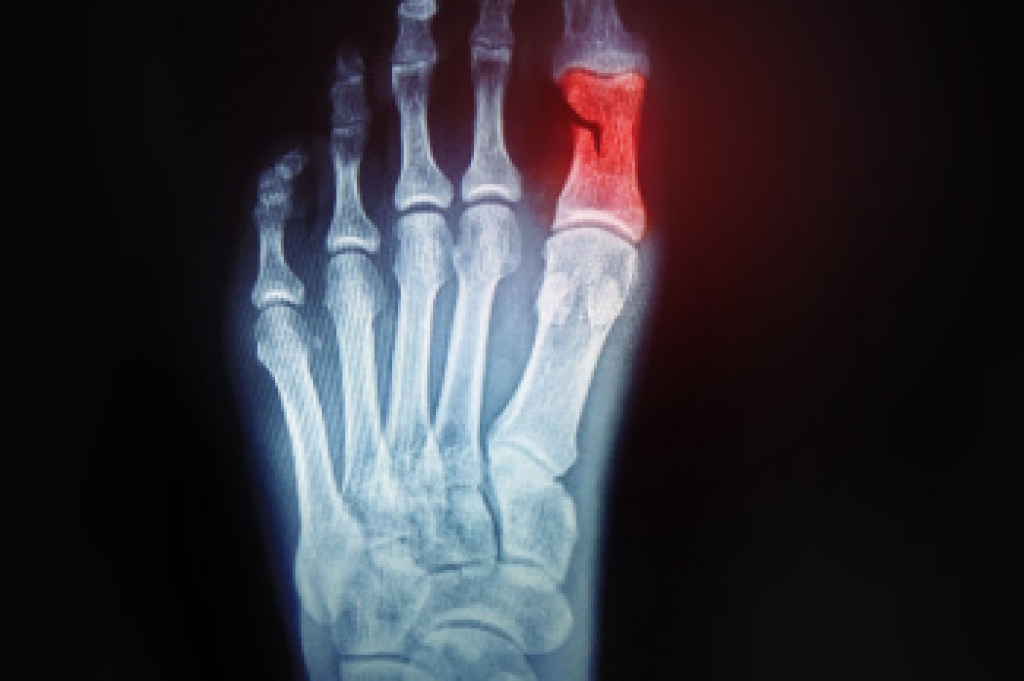

In some cases, surgical procedure may be needed to remove the toenail fungus. Consult with your podiatrist about the best treatment options for your case of toenail fungus.